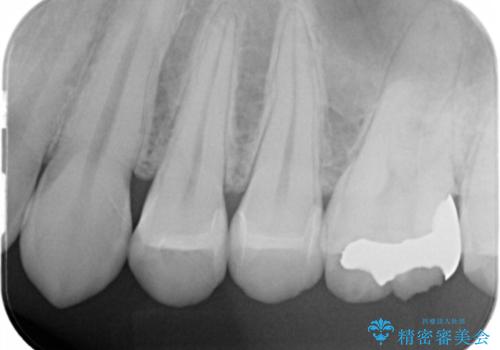

レントゲンで診査したら、歯と歯の間に虫歯(コンタクトカリエス)が見られたので

e-maxインレーで治療を行いました。

- e-maxインレー 7.7万円 ×2本費用は治療当時の料金となります